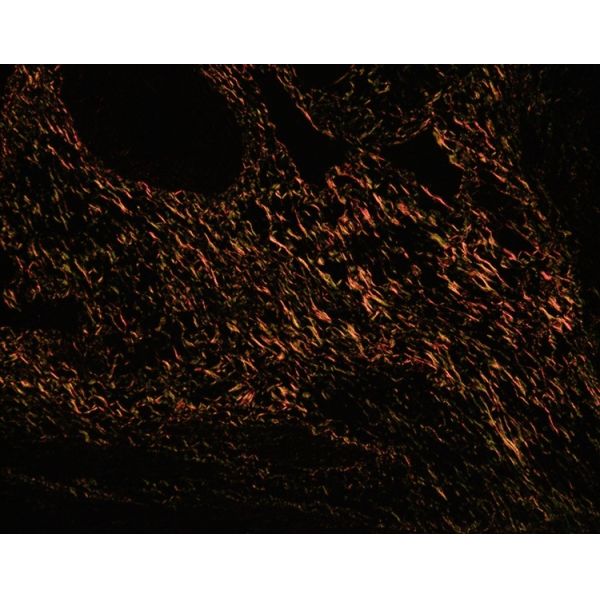

Under polarized light, collagen fiber tissues exhibit positive uniaxial birefringence. The basic groups in tissue cells adsorb and firmly bind to Sirius Red, enhancing the birefringence and allowing differentiation between different types of collagen fibers.

Under polarized light:

Type I collagen fibers exhibit strong birefringence, appearing bright orange-yellow or vivid red.

Type II collagen fibers exhibit very weak birefringence, appearing light red or bright white, with almost no staining.

Type III collagen fibers exhibit weak birefringence, appearing green.